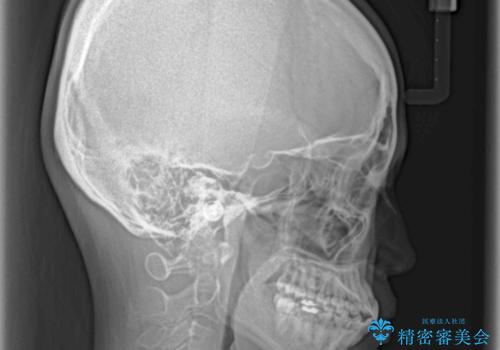

骨格的な問題を抱えた左奥以外は比較的早く咬み合わせが改善しましたが、左奥はどこで咬み合えば良いのか分からず、大変不便な思いをされていました。

ゴムかけにご協力いただき、最終的には反対咬合を改善することができ、患者様には大変満足していただきました。